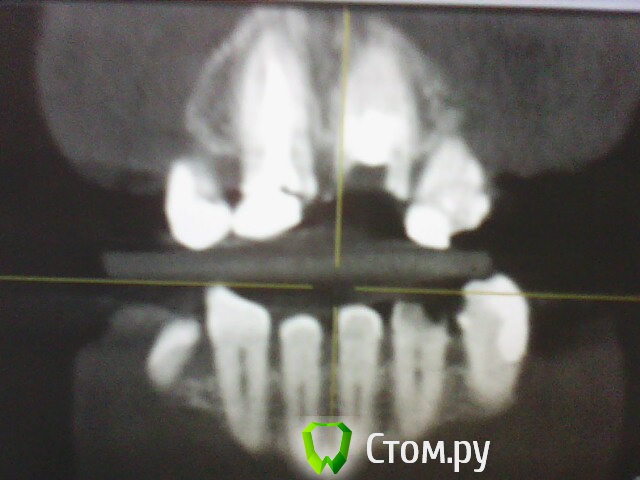

ОльгаS Опубликовано 7 октября, 2014 Поделиться Опубликовано 7 октября, 2014 Рентген показал что в зубом все в порядке, КТ - гранулему и что то там с корнем, если правильно поняла, какое то скрещивание: Ссылка на комментарий

IvanK Опубликовано 8 октября, 2014 Поделиться Опубликовано 8 октября, 2014 Очень может быть нужны другие срезы кт Ссылка на комментарий